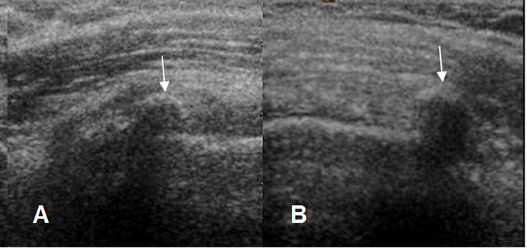

Fig 105. Irregularidad en la cortical.

A: Rx AP y B: Ecografía coronal. Irregularidad en el borde superior de la cabeza humeral, que se traduce en la ecografía, como imágenes ecogénicas. (Flechas delgadas). El tendón del supraespinoso ha perdido su convexidad superior, por ruptura parcial. (Flecha gruesa).